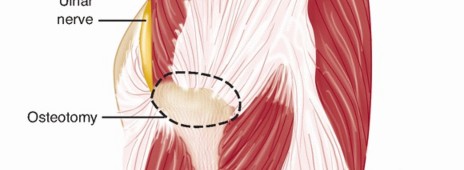

A longitudinal incision is made in the midline of the posterior aspect of the arm, from 8 cm below the acromion to the olecranon fossa (FIG 5A).

There is no true internervous plane; dissection involves separating the heads of the triceps brachii muscles, all of which are supplied by the radial nerve.

The medial head, which is the deepest, has a dual nerve supply (radial and ulnar nerves).

The outer layer consists of two heads: The lateral head arises from the lateral lip of the spiral groove and the long head arises from the infraglenoid tubercle of the scapula (FIG 5B).

The inner layer consists of the medial head, which arises from the whole width of the posterior aspect of the humerus below the spiral groove all the way down to the distal fourth of the bone.

The spiral groove contains the radial nerve; the radial nerve separates the origins of the lateral and medial heads (FIG 5C*).

To avoid iatrogenic nerve injury, the surgeon should never continue dissection down to bone in the proximal two-thirds of the arm until the radial nerve has been identified.